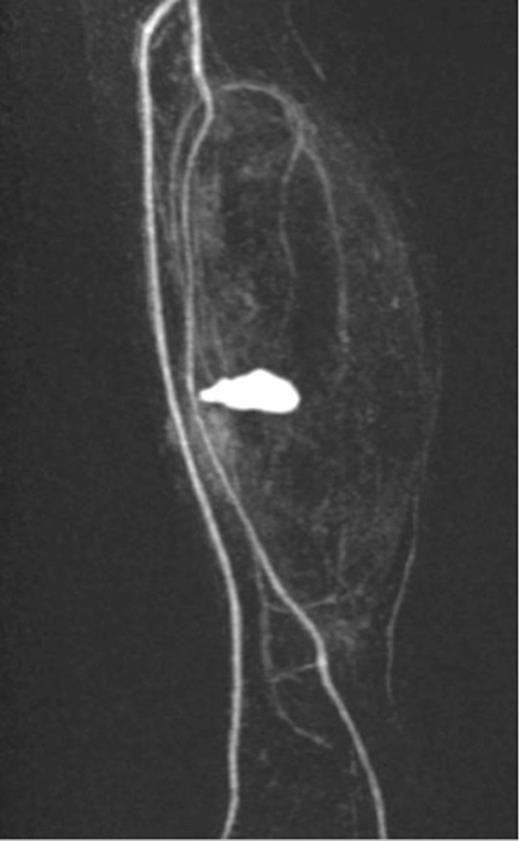

A 20-year-old man with no past medical history presented to the emergency department with non-displaced and closed transverse fracture of the left mid-tibial shaft and an intact fibula induced by a tackle during a football match. On examination, he had no neurovascular deficit and all crural pulses were palpable. His fracture was treated conservatively with a non-weight bearing above knee plaster cast later replaced by a below knee cast for a total period of 6 months. Upon examination during his attendance to the facture clinic, x-ray demonstrated no signs of fracture union. The subsequent magnetic resonance imagining (MRI) confirmed a nonunion of the fracture along with an ovoid 2.7 cm posterior compartment vascularized mass causing bowing of the interosseous septum with no evidence of avascularity of the bony margins (Fig. 1). This was confirmed to be a pseudoaneurysm originating from the PTA. An endovascular approach was adopted, and the pseudoaneurysm was injected with 2 ml of thrombin, filled with multiple coils and deployment of an angiography balloon (in the sac) (4 mm × 6 cm) for 7 min (Fig. 2). This resulted in complete cessation of the pseudoaneurysm with normal flow in the PTA (Fig. 3). The residual extravasated hematoma was later drained by an open approach. Follow-up x-ray (6 months) demonstrated complete union of the fracture site with no associated complications.

Complete resolution of the pseudoaneurysm and confirmed patent PTA.